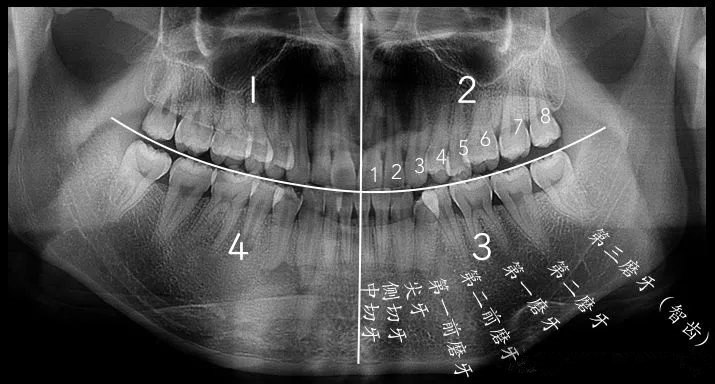

哪顆是智齒,從(cong) 全景片怎麽(me) 看